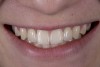

(6.) Six years post-operatively. Chipping noted on resin-based composites associated with nail biting habit. Bridge had not loosened.

Figure 6

Six years later, the patient was in his fourth year of college when he finally returned for implant placement (Figure 6). Interestingly, the provisional bridge had not come loose since it was bonded, even though the patient had a nail biting habit and had fractured most of the resin-based composite on the central incisors. He had also failed to wear his retainer, and as a result, the upper left lateral incisor had rotated slightly (Figure 6). In the right lateral incisor site, there was a horizontal deficiency in the bone and overlying soft tissue. A cone-beam computed tomography (CBCT) image was taken, and the area was evaluated for implant placement. There was enough native bone to place a 3 mm implant, but a connective tissue graft was needed to rebuild the deficient ridge. Unfortunately, when the patient presented for implant placement, it was during a holiday break from school and he needed to study. Therefore, the patient did not want to simultaneously augment with a connective tissue graft at the time of implant placement due to the pain associated with treatment. A 3.0 x 10 mm Astra Tech implant was placed, and the resin-bonded bridge was rebonded, utilizing the CoJet Silica, salinization, and the same dual-cured resin cement. Four months later, the patient returned for the connective tissue graft (Figure 7). The bridge was removed, the graft was performed utilizing a tunnel technique, and the bridge was rebonded as described earlier (Figure 8). After another four months, the patient returned during a two-week break. At this time, the implant was exposed, the tissue was manipulated with provisionals, and the final restorative work was completed (Figure 10 and Figure 11).